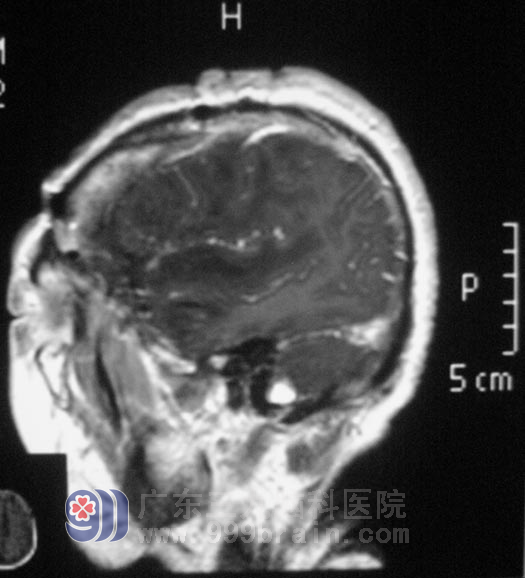

年近七旬的林奶奶一向身体很好,三天前突然出现头痛、头晕,双下肢乏力行走困难,在当地医院行头颅MR检查,结果提示右侧颞部占位。

入住广东三九脑科医院综合神经外科,完善相关检查后,鲁明主任主刀在全麻下行右侧颞部占位切除术,术中导航定位,显微镜下见肿瘤呈红白色,质地中等,血运一般,与脑组织边界较清,予镜下行肿瘤全切。病理结果为:混合型脑膜瘤 WHO I级。经过治疗,林奶奶行走如初,没有任何后遗症。